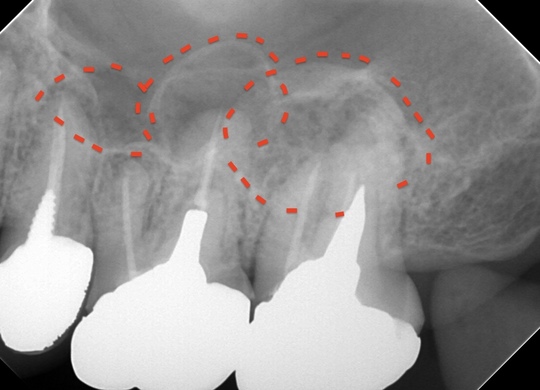

自費根管治療症例1 治療前

左上の奥歯の腫れと噛んだ時の痛みで来院。

根の先にうみが溜まっています

副鼻腔の骨の壁を突き破っています